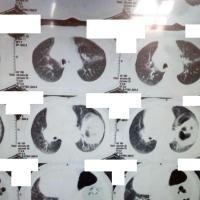

男,45岁,咳嗽,咳痰1个月,发热,盗汗,体重下降5公斤,肺结核病史30年.右肺下叶病变性质待查?